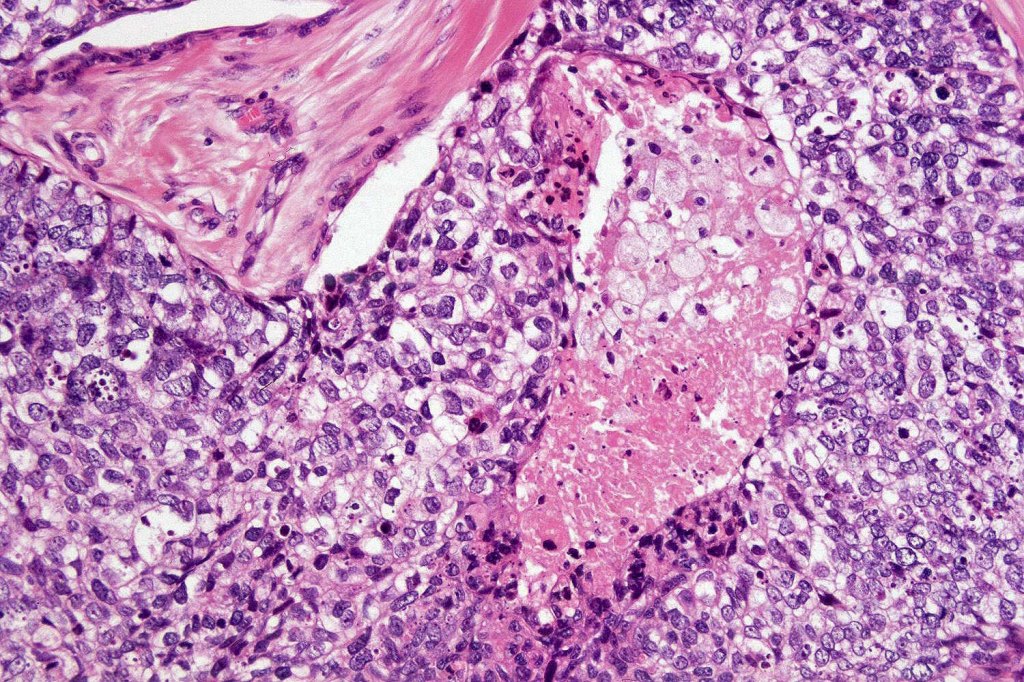

•Well differentiated lobular growth pattern though to a poorly differentiated tumor often showing a diffuse, infiltrating border which may extend into the subcutaneous fat

•Comedo type necrosis commonly present

•Tumors are composed of an admixture of darkly staining basaloid cells with hyperchromatic or vesicular nuclei and more obvious sebaceous cells with eosinophilic, bubbly, multivacuolated cytoplasm frequently indenting the nucleus (scalloped)

•Often mitoses are numerous and abnormal forms evident

•Focal squamous differentiation with keratinization can be present resulting in confusion with squamous cell carcinoma